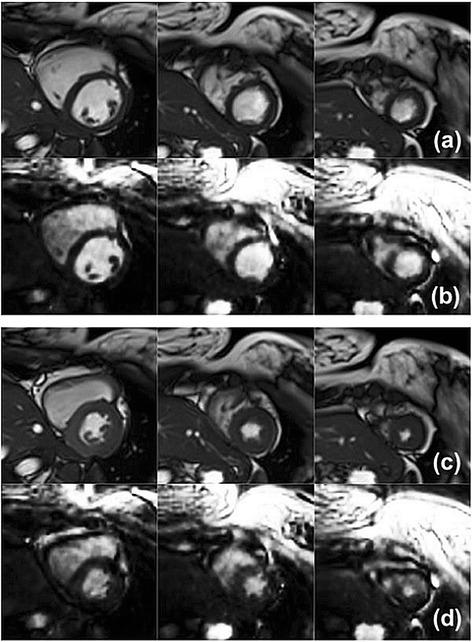

The standard clinical acquisition for left ventricular functional parameter analysis with cardiovascular magnetic resonance (CMR) uses a multi-breathhold multi-slice segmented balanced SSFP sequence. Performing multiple long breathholds in quick succession for ventricular coverage in the short-axis orientation can lead to fatigue and is challenging in patients with severe cardiac or respiratory disorders. This study combines the encoding efficiency of a six-fold undersampled 3D stack of spirals balanced SSFP sequence with 3D through-time spiral GRAPPA parallel imaging reconstruction. This 3D spiral method requires only one breathhold to collect the dynamic data.

Ten healthy volunteers were recruited for imaging at 3 T. The 3D spiral technique was compared against 2D imaging in terms of systolic left ventricular functional parameter values (Bland-Altman plots), total scan time (Welch's t-test) and qualitative image rating scores (Wilcoxon signed-rank test).

Systolic left ventricular functional values were not significantly different (i.e. 3D-2D) between the methods. The 95% confidence interval for ejection fraction was -0.1 ± 1.6% (mean ± 1.96*SD). The total scan time for the 3D spiral technique was 48 s, which included one breathhold with an average duration of 14 s for the dynamic scan, plus 34 s to collect the calibration data under free-breathing conditions. The 2D method required an average of 5 min 40s for the same coverage of the left ventricle. The difference between 3D and 2D image rating scores was significantly different from zero (Wilcoxon signed-rank test, p < 0.05); however, the scores were at least 3 (i.e. average) or higher for 3D spiral imaging.

The 3D through-time spiral GRAPPA method demonstrated equivalent systolic left ventricular functional parameter values, required significantly less total scan time and yielded acceptable image quality with respect to the 2D segmented multi-breathhold standard in this study. Moreover, the 3D spiral technique used just one breathhold for dynamic imaging, which is anticipated to reduce patient fatigue as part of the complete cardiac examination in future studies that include patients.